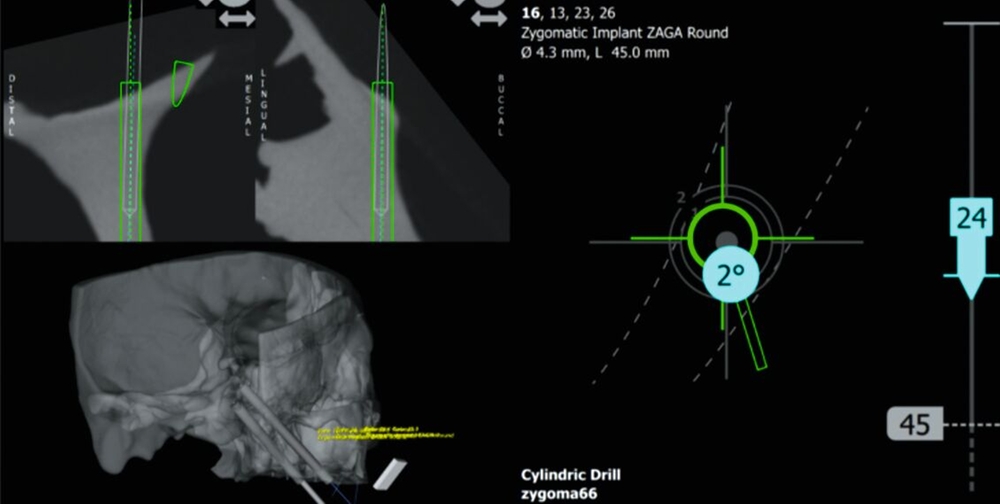

Um festzustellen, ob ein Patient mit atrophem Oberkiefer oder Oberkieferdefekt für die Versorgung mit Zygoma-Implantaten geeignet ist, sind vor allem dreidimensionale radiologische Untersuchungen notwendig. So wird eine minimale Dimension des Jochbeinkörpers von 7 mm empfohlen, um die Implantate apikal primärstabil verankern zu können. Zur weiteren Planung und Durchführung bietet sich der von der Zygomaanatomie geführte Zugang („Zygoma Anatomy Guided Approach“ - ZAGA) nach Aparicio an [Aparicio, 2011]. Jener beschreibt den Grad der Konkavität der lateralen Kieferhöhlenwand und den Grad der palatinalen Resorption des verbleibenden Kieferkamms.

Die ZAGA-Klassifizierung reicht von 0-4 (Abbildung 6). Der Zahnarzt importiert den 3-D-Scan des Patienten in eine Planungssoftware seiner Wahl (zum Beispiel coDiagnostiX®, Dental Wings GmbH, Chemnitz, Deutschland - Abbildung 7) und simuliert das Zygoma-Implantat an der gewünschten Position. Auf diese Weise kann er visualisieren und voraussagen, ob die Plattform des Zygoma-Implantats in der Maxilla des Patienten stabilisiert wird und ob der mittlere Teil des Zygoma-Implantats vollständig innerhalb, teilweise innerhalb oder vollständig außerhalb der Kieferhöhle liegt. Wie von Aparicio berichtet, hatten 93,5 Prozent der untersuchten Patienten eine ZAGA 0-3 Anatomie und nur 6,5 Prozent eine Topografie, die mit ZAGA 4 übereinstimmte [Aparicio, 2011].

Von Vorteil bei der Insertion von Zygoma-Implantaten ist die navigierte Chirurgie (Abbildung 9). So wurden in einer Studie 188 Zygoma-Implantate mit einer Überlebensrate von 98,4 Prozent via Echtzeitnavigation mit vielversprechender, hoher Genauigkeit platziert [Wu et al., 2022]. Ähnliche Ergebnisse lieferte auch ein systematischer Review aus zwölf Artikeln mit 150 Zygoma-Implantaten, die mithilfe eines computergestützten Navigationsansatzes inseriert wurden [Ramezanzade et al., 2021].

Die Versorgung mit Zygoma-Implantaten im Vergleich zu herkömmlichen Implantaten erfordert erfahrene Chirurgen und Prothetiker, um die Behandlung erfolgreich auf höchstem Niveau durchführen zu können. Darüber hinaus zeigt die Platzierung von Zygoma-Implantaten eindrucksvoll den Nutzen der computergestützten Chirurgie, die hier als zuverlässiger Ansatz zur Verbesserung der Genauigkeit und zur Vermeidung chirurgischer Komplikationen als Therapiestandard gesehen werden sollte [Ramezanzade et al., 2021; Kämmerer et al., 2022].